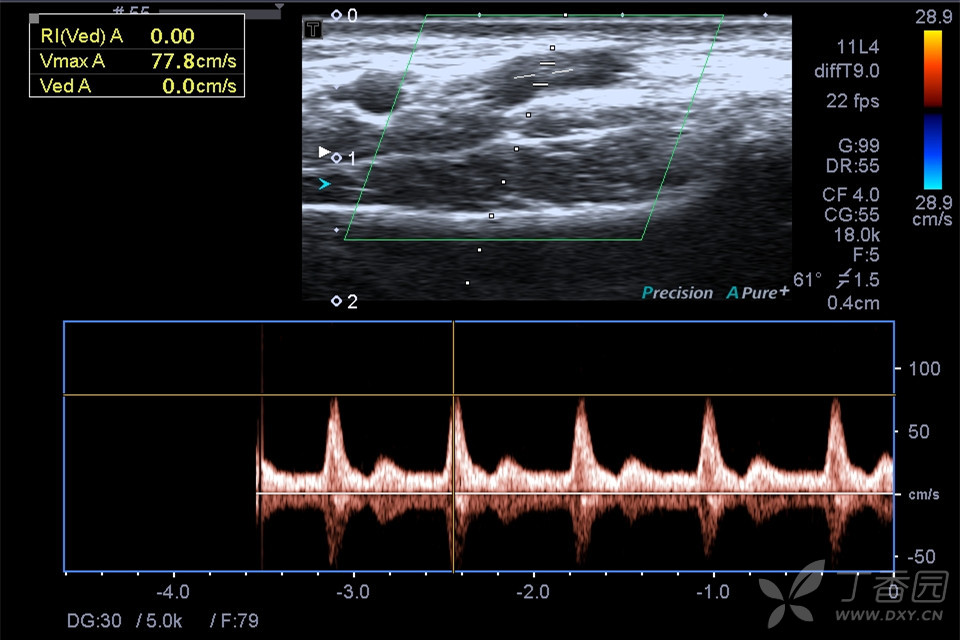

图三:动静脉瘘频谱.

注意收缩期与舒张期转变处!频谱图上一目了然